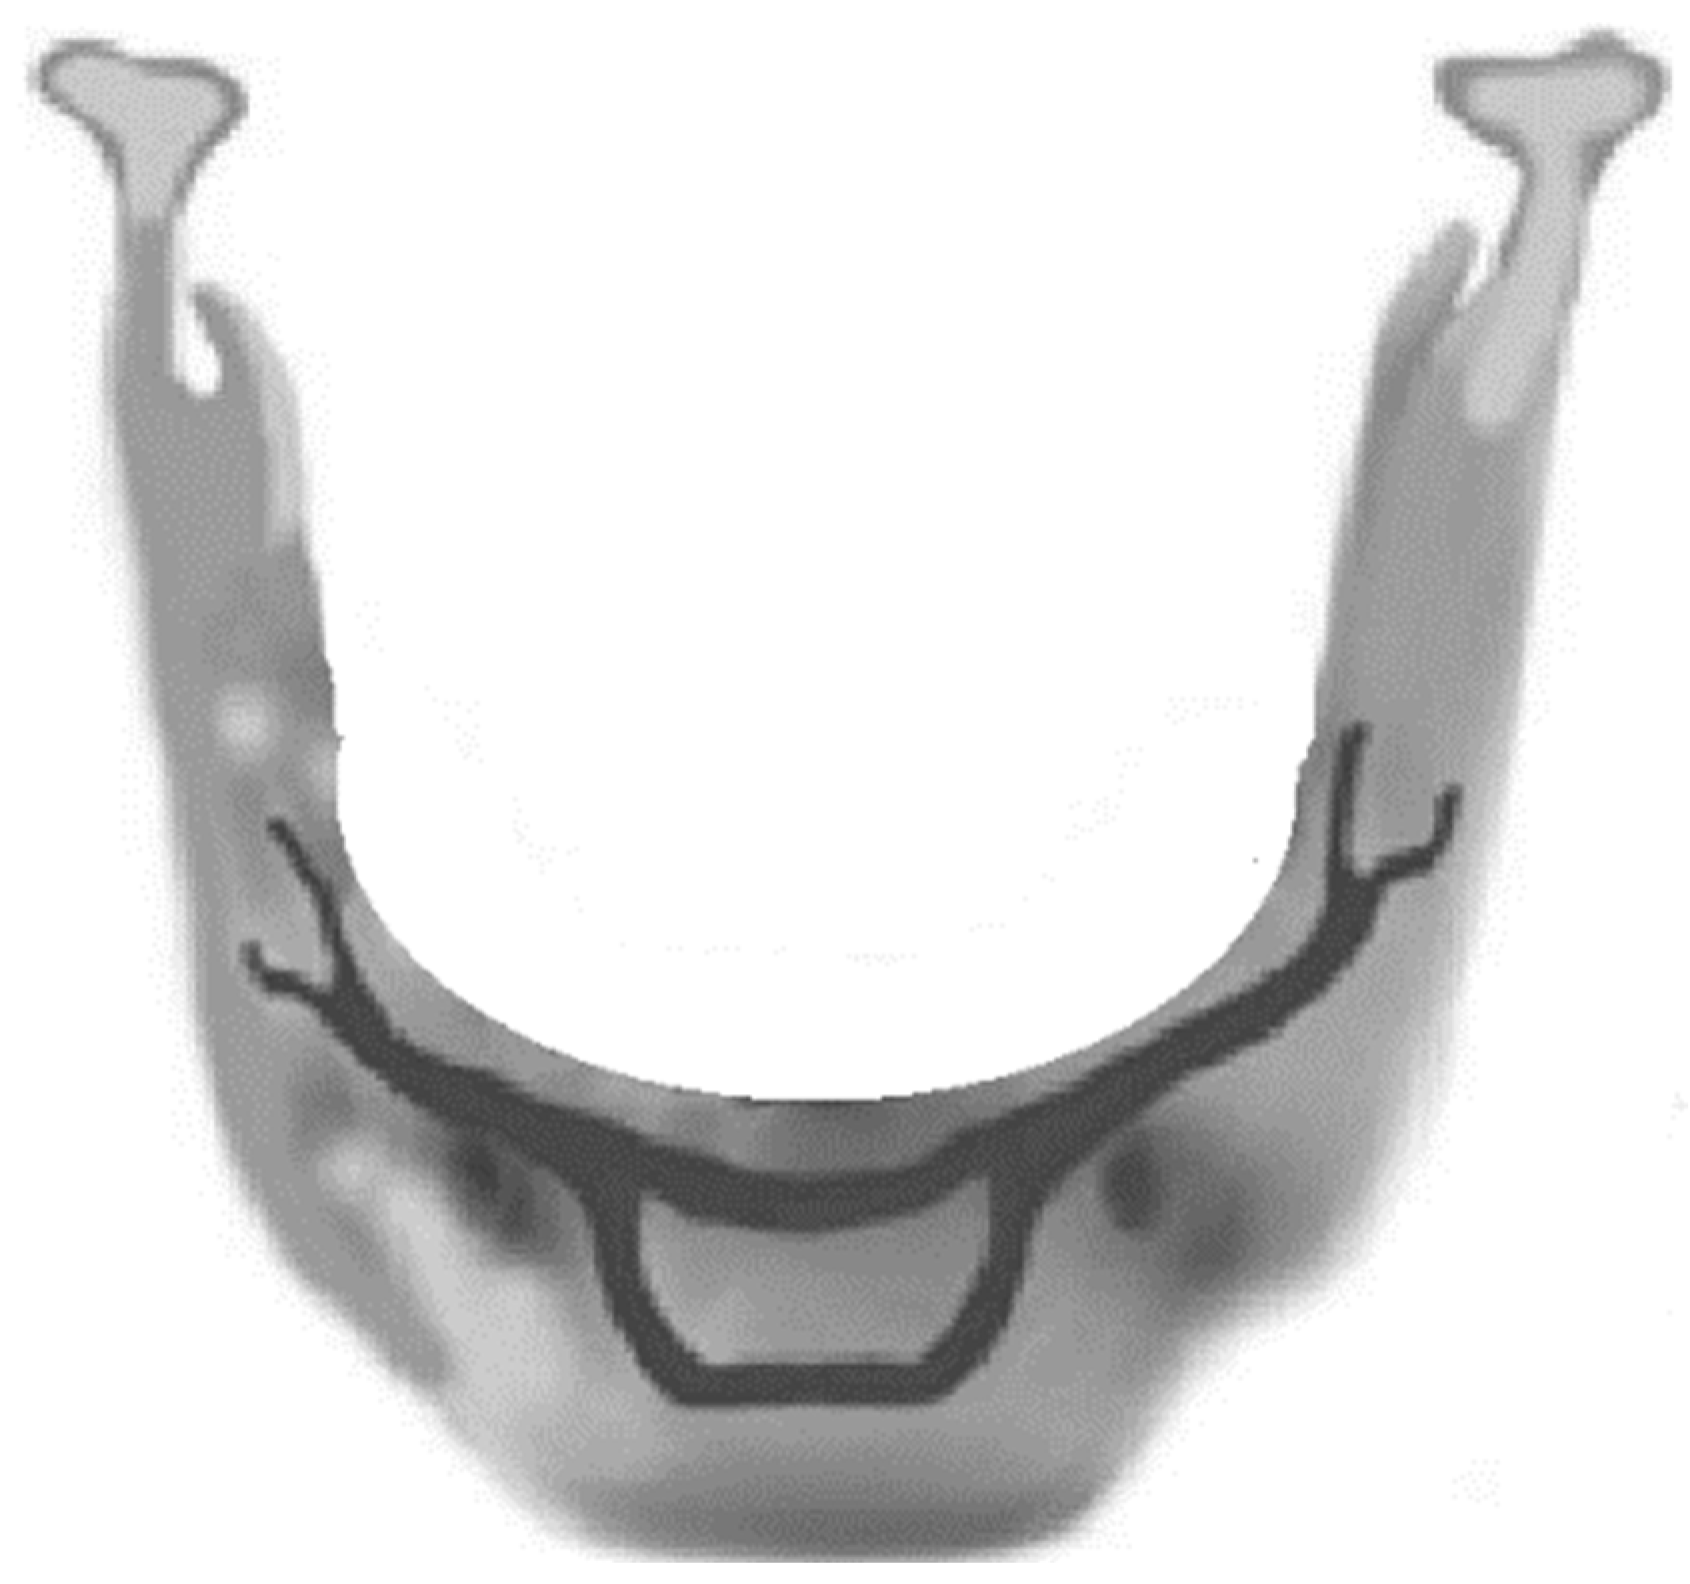

2.1. Model Description

2.3. Boundary Conditions